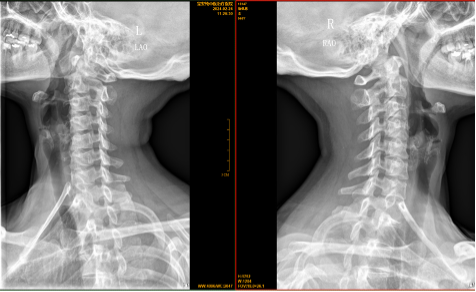

【影像】 颈椎X线片见颈椎平直,向右侧弯,C5-6椎间隙狭窄,椎体后缘骨质增生。C5-6、C6-7右侧椎间孔狭窄。右侧寰枢外侧关节对合不全,左侧显示不清,枢椎棘突偏左。

右侧风池穴压痛(+)、右侧头后大直肌紧张压痛(+),X线片见右侧寰枢外侧关节对合不全、左侧显示不清、枢椎棘突偏左,考虑“寰枢关节紊乱”。患者没有颈枕部疼痛、旋转受限、头晕、头痛、失眠等相应症状,不能下 “寰枢关节紊乱综合征” 的临床诊断。